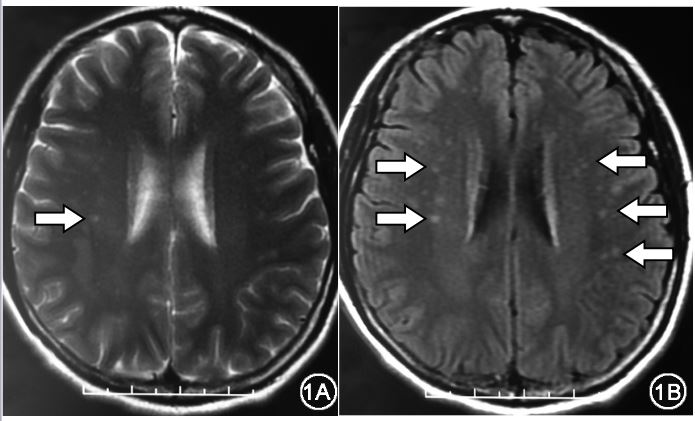

头颅MRI显示42例(43.3%)患者半卵圆中心内可见多个散在点状的长T2或液体衰减反转恢复 (FLAIR) 序列上呈高信号,而在T1WI序列呈等信号。

图 头MRI